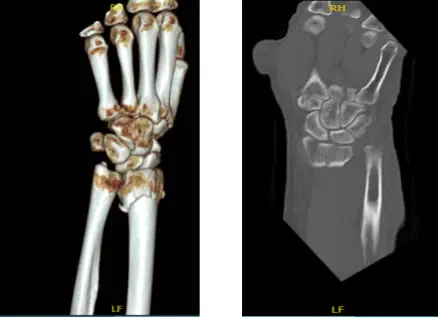

The patient is a 63 year-old female seen in the office with left wrist pain due to falling on the wrist. She was seen at Mather by Dr. Karkare where reduction was done. She got a CT done.

CT were reviewed and discussed by the doctor; there is a comminuted fracture of the distal radius with intra-articular extension where displacement measures approximately 1 mm. Maximal fracture displacement measures approximately 9 mm.

Approximately 20 degrees of palmar angulation are present. A displaced fracture of the ulnar styloid is also identified. Mild degenerative changes are present at the triscaphe and first carpometacarpal joints.